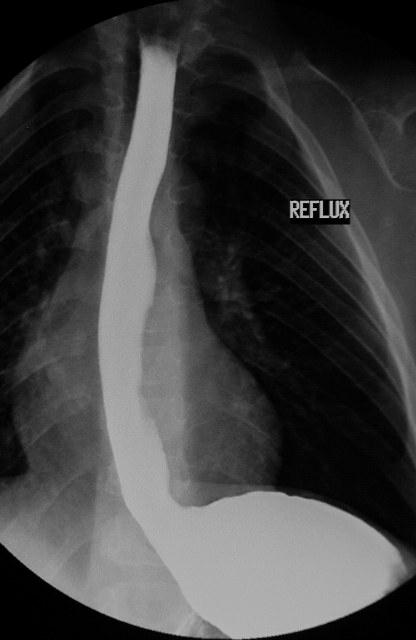

Рентгеновское исследование с использованием контраста. В качестве контраста используют Барий. Это жидкость белого цвета похожая на молоко. По вкусу напоминает мел. Эта жидкость абсолютно не токсична, не всасывается в кишечнике, зато хорошо видна на рентгеновском снимке (белого цвета). Для этой процедуры Вас попросят выпить стакан Бариевой смеси и лечь на спину. В этом положении Вам сделают рентген снимок, где будет виден патологический заброс бария из желудка в пищевод.